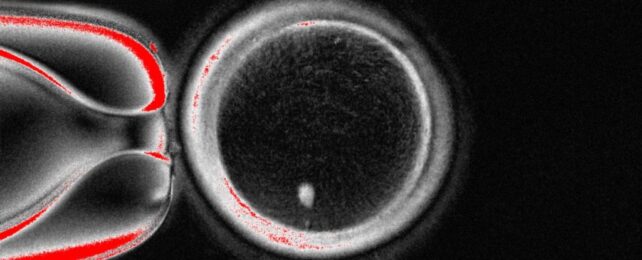

Working Egg Cells Made Using DNA From Human Skin in World First

Scientists have created human egg-like cells – capable of fertilization – out of skin cells, in a potential breakthrough for fertility treatments.

"While this is still very early laboratory work, in the future it could transform how we understand infertility and miscarriage, and perhaps one day open the door to creating egg- or sperm-like cells for those who have no other options," says fertility specialist Ying Cheong of the University of Southampton.